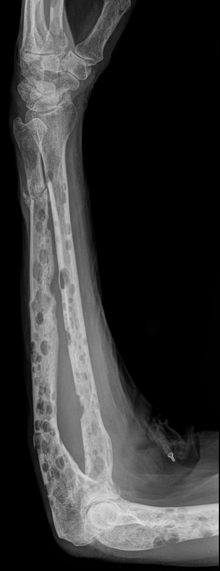

Nach der klonalen Vermehrung einer entarteten Plasmazelle kommt es zur Infiltration des Knochenmarks mit folgender Zerstörung des Knochens und Verdrängung der normalen Hämatopoese (Blutbildung). Hierbei scheiden die malignen Zellen Wachstumsfaktoren und Zytokine aus, welche die Osteoklasten aktivieren (u. a. OAF), was letztlich zu einem Knochenabbau führt. Dies führt zu einer allgemeinen Osteoporose sowie zu den charakteristischen, im Röntgenbild sichtbaren Knochenschäden, die im Gegensatz zu Knochenmetastasen wie ausgestanzt dargestellt werden. Es fehlt der bei Knochenmetastasen sonst vorhandene Saum aus reaktiven Zellen („osteoblastischer Randsaum“). Dies ist auch der Grund dafür, dass sich die Knochenveränderungen bei einem Plasmozytom nicht im Knochenszintigramm darstellen können. Insgesamt entwickeln etwa 60 % der Patienten Knochenveränderungen.

- Knochenschmerzen und Knochenbrüche durch Auflösung des Knochengewebes (Osteolysen). Osteolysen im Schädelknochen stellen sich im Röntgenbild als sogenannter „Schrotschussschädel“[8] dar;

Osteolysen lassen sich mit konventioneller Röntgen-Untersuchung der Knochen nachweisen. Das Skelettszintigramm zeigt oft keine Aktivitätsänderung im osteolytischen Bereich, ist hier also nicht verlässlich. Ein Knochenszintigramm eignet sich aber zum Nachweis von Knochenbrüchen (pathologische Fraktur) aufgrund der Infiltration durch das Plasmozytom. Zur Frühdiagnose einer Plasmozytominfiltration in den Knochen kann das MRT beitragen, hier zeigt sich auch die Reaktion im Weichteilmantel, bevor es zu Osteolysen gekommen ist.